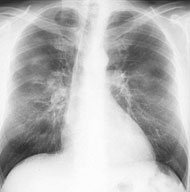

Ein 58-jähriger, sportlich aktiver Mann sucht Sie in der Sprechstunde auf. Er klagt über eine Leistungsminderung und Husten mit etwas weisslichem Auswurf seit ca. 2-3 Wochen. Dazu subfebrile Temperaturerhöhung.

In der Anamnese erfahren Sie, dass der Patient früher geraucht hat (30 packyears), seit 10 Jahren allerdings nicht mehr. Kardiopulmonale Vorerkrankungen werden verneint. Die Lungenauskultation zeigt keine pathologischen Befunde.

Sie beschliessen, ein Thorax-Röntgenbild durchzuführen:

Thorax pa

Wie beurteilen Sie das Röntgenbild in Kombination mit der Klinik?